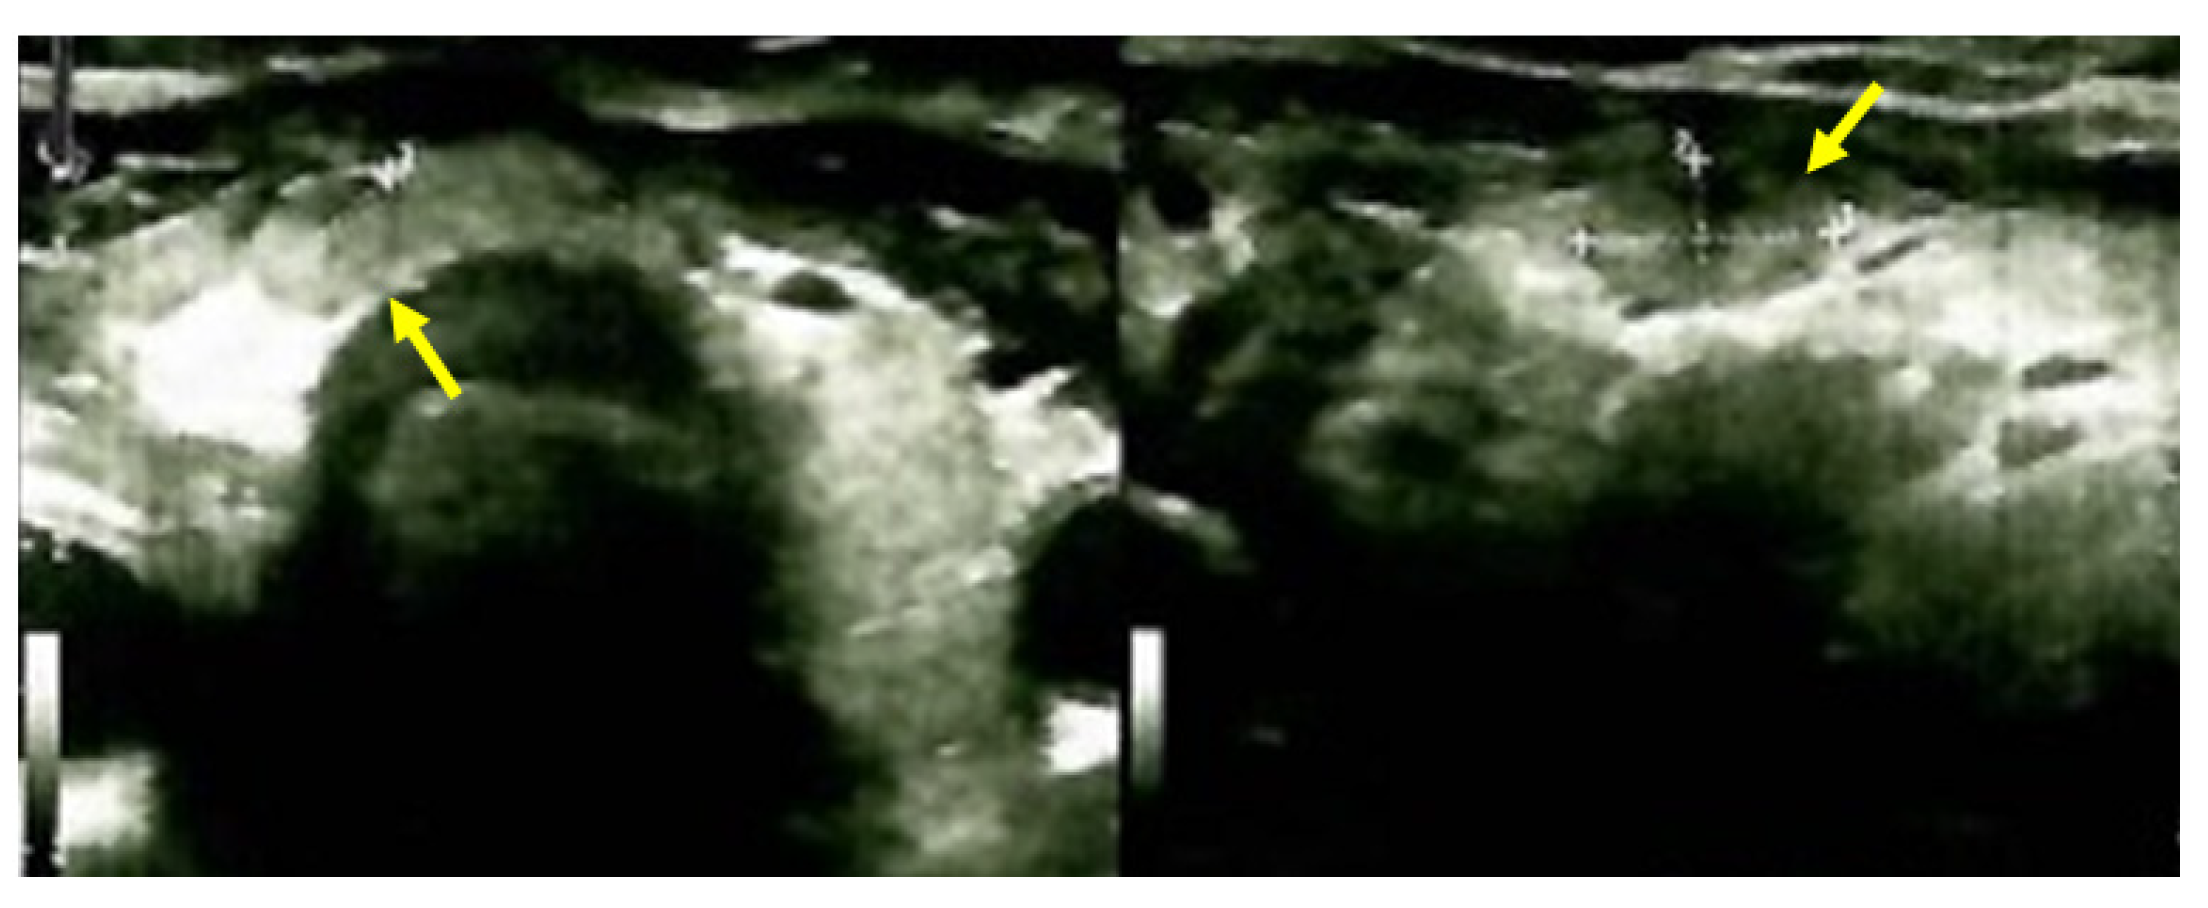

A clinical improvement was registered early after parathyroidectomy with the remission of the presurgery bone complains. The lady was offered therapy with calcitriol 0.25 μg/day, cholecalciferol 2000 UI/day, and oral calcium intake. No thyroxine replacement was necessary. No other postoperative complications were registered. No specific intervention was considered for the brown tumors other than managing the underlying parathyroid/mineral metabolism status according to a lifelong surveillance under these specific circumstances (Figure 11).

Figure 11.

Neck ultrasound after right subtotal thyroidectomy and right inferior parathyroidectomy: an isoechoic and relatively homogeneous thyroid pattern with an intensely vascularized, inhomogeneous nodule of 0.91 by 0.54 by 0.78 cm (yellow arrow) at the right lobe-isthmus junction, which required follow-up; the images did not suggest another parathyroid tumor was present.